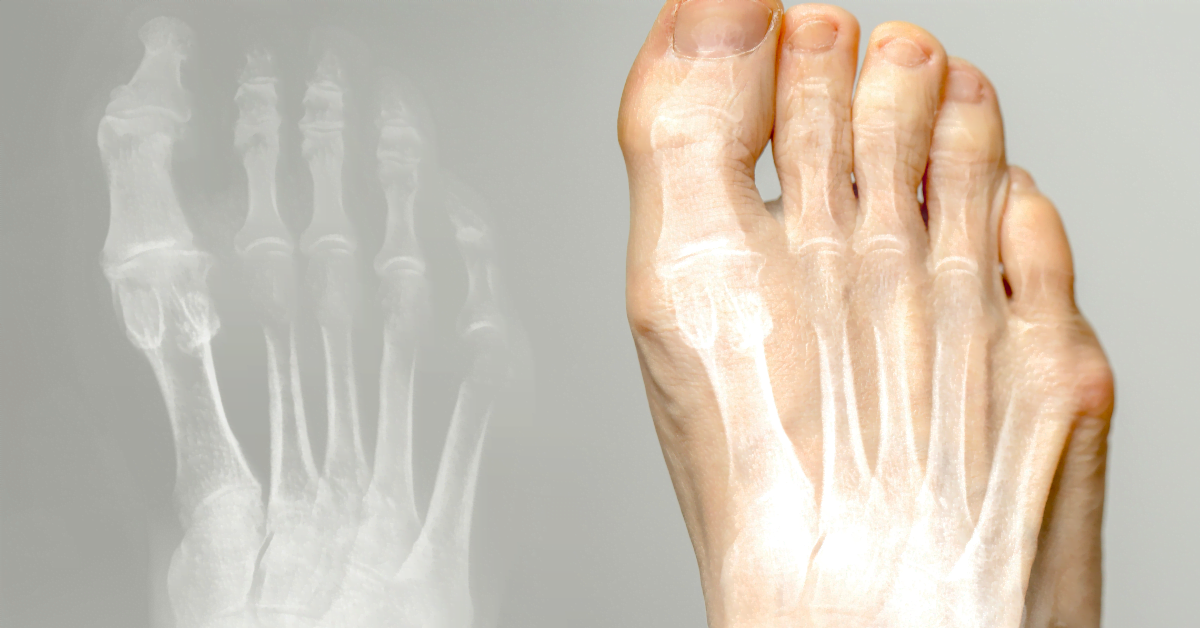

Hallux valgus (knobbelteen) is een aandoening waarbij de grote teen naar binnen wijst en een knobbeltje vormt aan de basis. Het kan pijn en ongemak veroorzaken. Hier lees je oorzaken, behandeling en preventie.

De grote teen buigt naar de andere tenen, waardoor een voetknobbel ontstaat. Oorzaken: smalle schoenen, hoge hakken, erfelijkheid, platvoeten of artritis. Slecht schoeisel veroorzaakt druk en wrijving, wat kan leiden tot slijmbeursontsteking.

Hallux valgus is een scheefstand van de grote teen naar binnen, met een knobbel aan de basis. Vaak door smalle schoenen, hoge hakken of erfelijkheid. Kan pijn en slijmbeursontsteking veroorzaken.